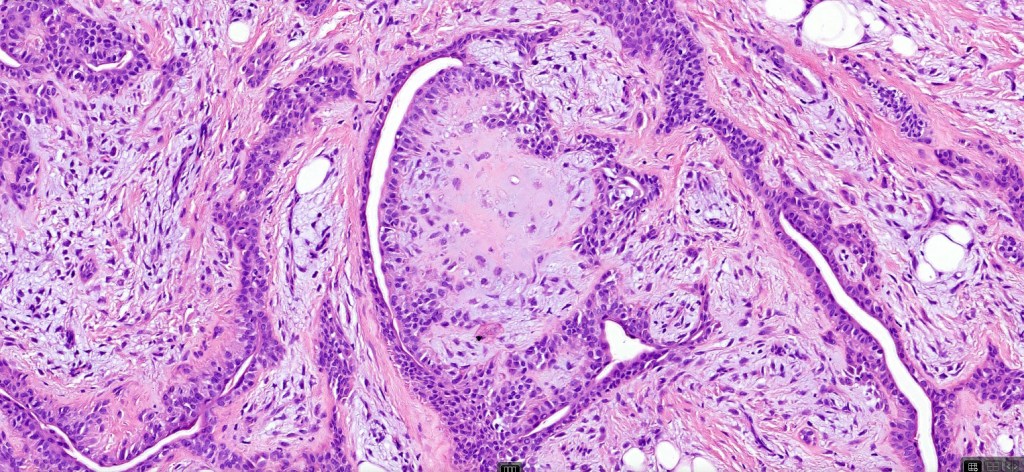

•Mixed epithelial component including nests & cords of epithelium with abundant, eosinophilic cytoplasm & small vesicular nuclei

•Clear cell change

•Glandular differentiation sometimes showing apocrine differentiation

•Myoepithelial layer in glandular foci

•Plasmacytoid myoepithelial cells; clear cell change

•Follicular & sebaceous differentiation

•Keratocysts & squamous foci